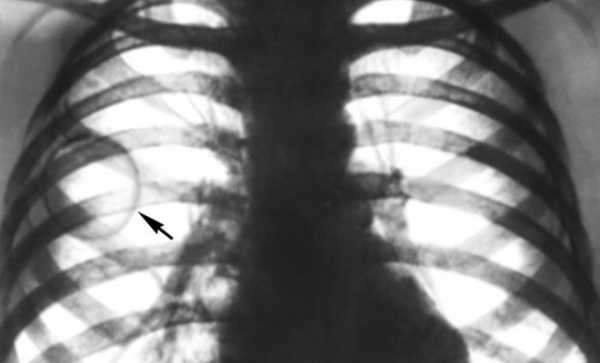

Рентгенокомпьютерная томография — один из методов диагностики

Диагностика этой болезни предусматривает инвазивные и неинвазивные методы. К информативным неинвазивным методам относятся УЗИ, рентгенокомпьютерная томография, магнитнорезонансная томография; среди инвазивных – чрескожная пункция и аспирация.